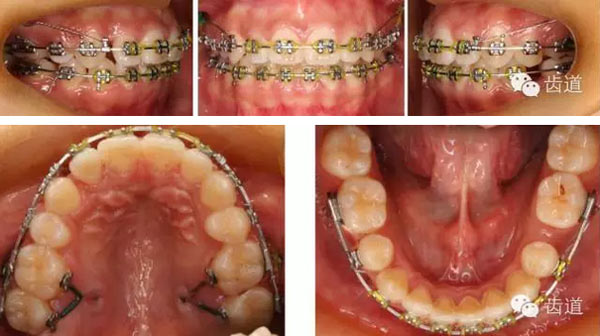

上頜第一與第二磨牙間頰腭側(cè)植入微種植體支抗。

壓低上磨牙,內(nèi)收上前牙,遠(yuǎn)中移動(dòng)左上牙列。

矯治過(guò)程